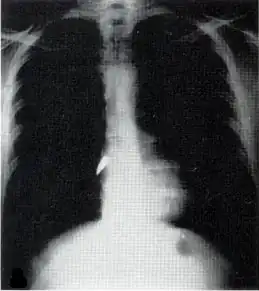

Рентгеновский снимок, показывающий пулю (белое пятно) в сердце

Большинство проникающих травм являются ранениями в грудную клетку и имеют уровень смертности менее 10 %[15]. Проникающее ранение грудной клетки может повредить жизненно важные органы, такие как сердце и лёгкие, и может помешать дыханию и кровообращению. Травмы лёгких, которые могут быть вызваны проникающим ранением, включают разрыв лёгочной артерии (порез или разрыв), ушиб легкого, гемоторакс (скопление крови в грудной полости за пределами легкого), пневмоторакс (скопление воздуха в грудной клетке) и гемопневмоторакс (скопление как крови так и воздуха в грудной клетке). Могут возникнуть сосательные раны на груди и натяжение пневмоторакса .

Проникающее ранение может также вызвать травмы сердца и системы кровообращения. Когда сердце пробито, оно может обильно кровоточить в грудную полость, если мембрана вокруг него (перикард) значительно разорвана, или может вызвать тампонаду перикарда, если перикард не разрушен[16]. В перикардиальной тампонаде кровь выходит из сердца, но задерживается внутри перикарда, поэтому между перикардом и сердцем нарастает давление, сжимая сердце и мешая его работе. Переломы рёбер обычно вызывают проникающее ранение грудной клетки когда острая кость прокалывает ткани.